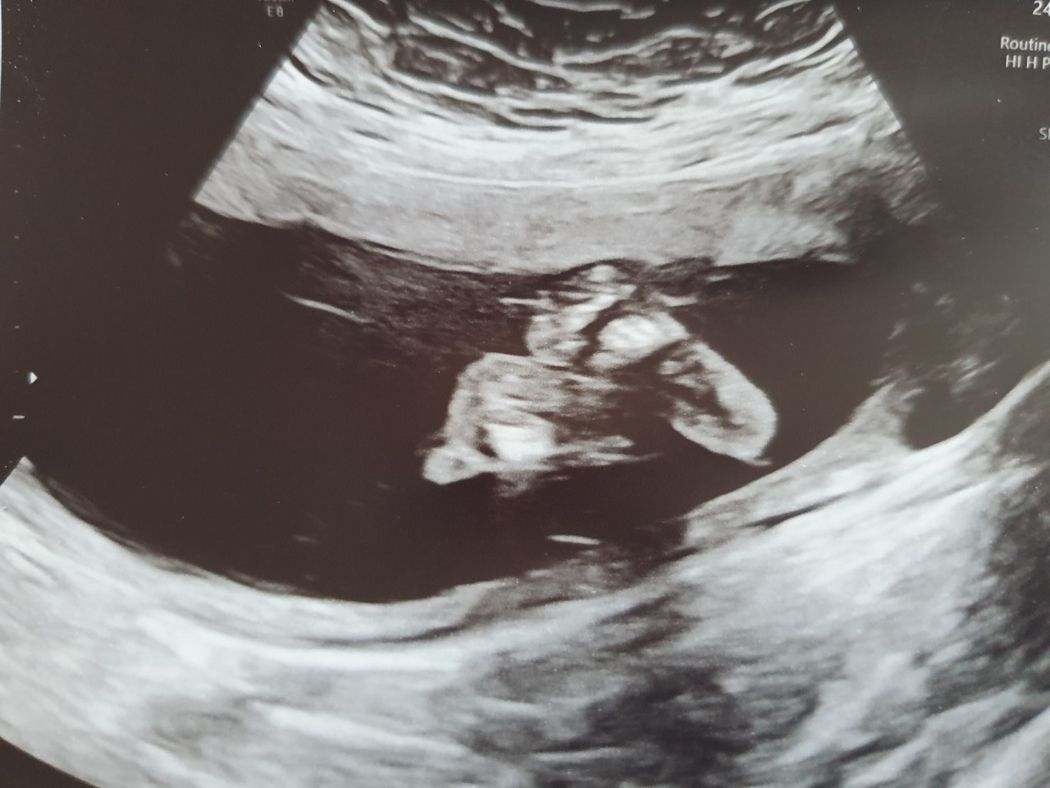

Thankfully, nothing went wrong, and Danielle is now 24 weeks pregnant with a baby girl.

“For the first few weeks I was so nervous, but now I'm excited," she said.

She added: “It felt amazing to see her heart beat for the first time and my little girl is giving me a hard time with all the kicking. She's always booting me – but I wouldn't have it any other way."

Now Danielle cannot wait to become a wife and mother – although she and Ed have agreed to put their wedding on hold for a while.